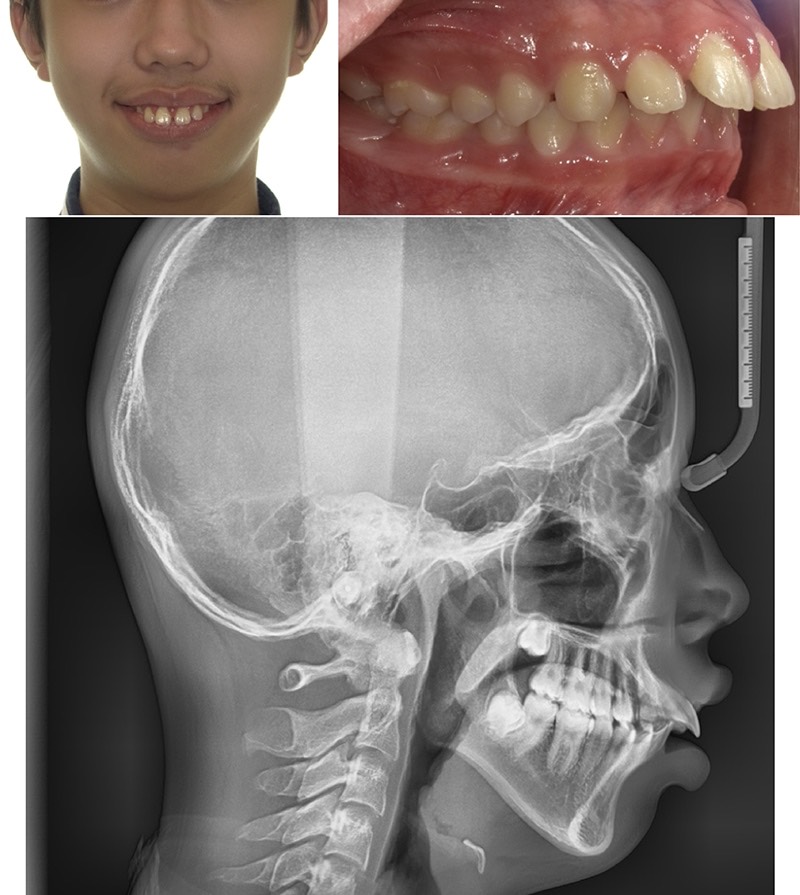

下圖為骨性暴牙+小下巴的案例,這種情況上下顎牙齒差距非常大,會加重外觀的暴牙感覺,療程設計也特別困難。

第二種暴牙原因屬於肌功能類型,最常聽到的如口呼吸(習慣性用嘴巴呼吸),嘴巴長期開開而造成舌頭位置低並前頂牙齒。

上面提到當牙弓變成V字型時,門牙就容易往外飛形成暴牙。牙弓被壓成V型也有許多可能的原因,甚至還有一說是趴睡會造成這個結果,但事實上並沒有明確醫學根據。